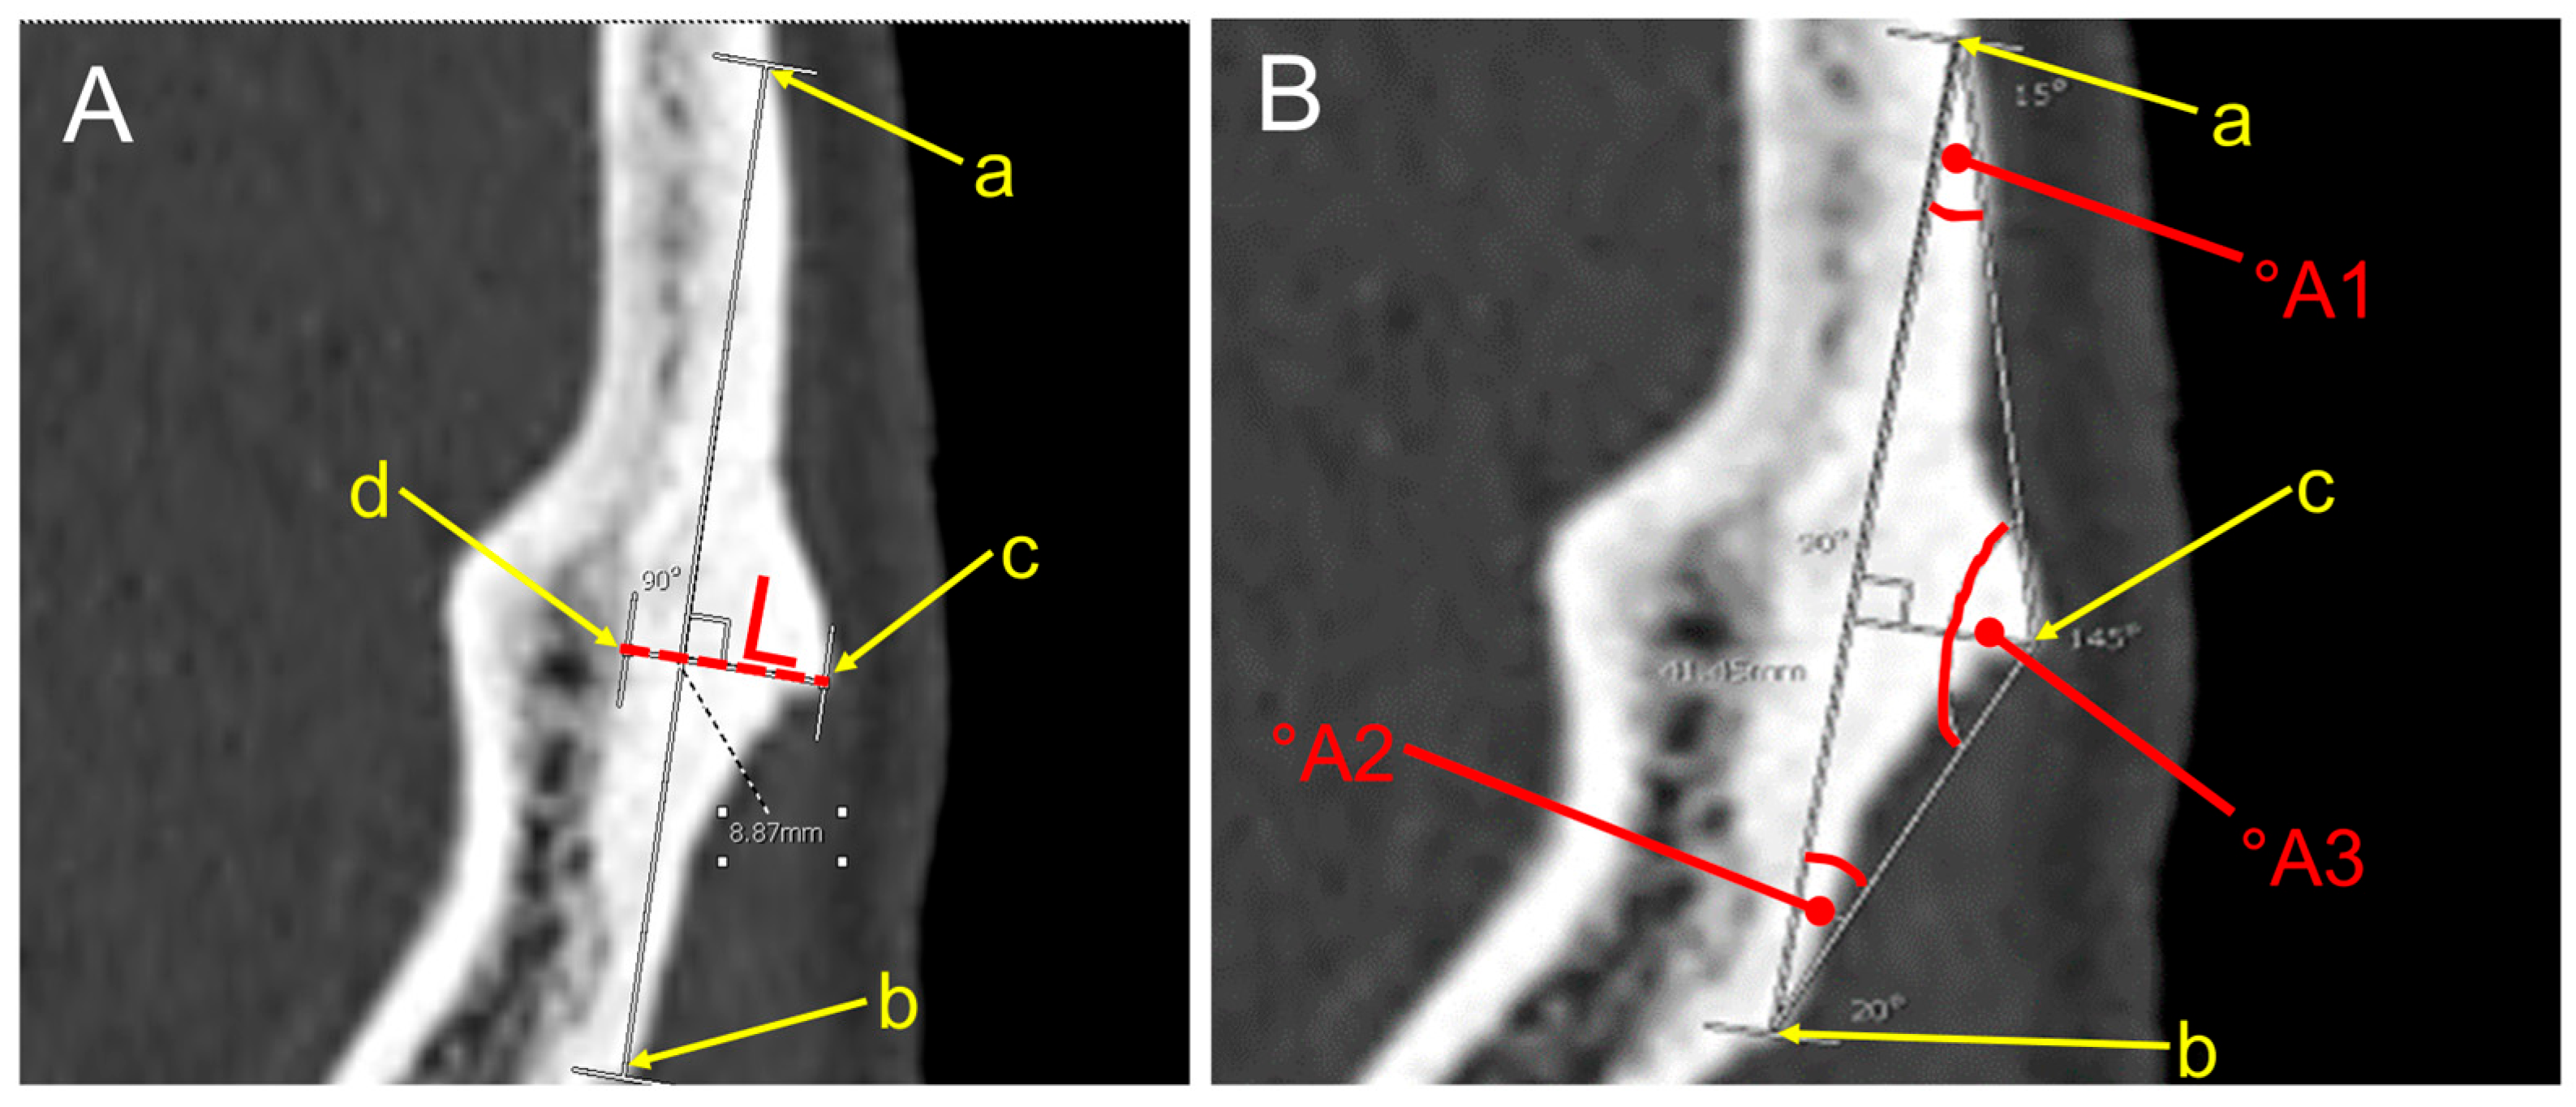

2.5. Morphometric Measurements

| Age Range (Years) | Morphometrics and Angles of EOP Type II (Means ± S.D.) | |||||||

|---|---|---|---|---|---|---|---|---|

| Female | Male | |||||||

| L (mm) | A1 (°A) | A2 (°A) | A3 (°A) | L (mm) | A1 (°A) | A2 (°A) | A3 (°A) | |

| 18–30 (n, 185) | 5.8 ± 0.2 | 19.6 ± 0.7 | 19.9 ± 0.8 | 140.5 ± 0.9 | 7 ± 0.2 | 23.5 ± 0.9 | 23.5 ± 1.1 | 133 ± 1.3 |

| 31–40 (n, 53) | 6.1 ± 0.5 | 18.3 ± 1 | 23.9 ± 5.4 | 137.89 ± 5.8 | 7.2 ± 0.4 | 25.3 ± 1.2 | 21.7 ± 1.1 | 132.9 ± 1.6 |

| 41–50 (n, 78) | 5.7 ± 0.5 | 18.2 ± 1.3 | 20.1 ± 2.4 | 141.7 ± 2.5 | 7.6 ± 0.5 | 23.8 ± 1.4 | 23.4 ± 1.4 | 132.8 ± 1.9 |

| 51–60 (n, 93) | 5.3 ± 0.2 | 18.1 ± 1.1 | 20.1 ± 1 | 141.8 ± 1.1 | 7 ± 0.4 | 23.5 ± 1.3 | 23.1 ± 1.2 | 133.4 ± 1.6 |

| >60 (n, 341) | 5.6 ± 0.2 | 19.4 ± 0.7 | 19.2 ± 0.5 | 141.4 ± 0.8 | 7 ± 0.2 | 22.8 ± 0.8 | 21.8 ± 0.7 | 135.4 ± 1 |

| Genders | Morphometry of EOP: Type II (Crest) | |||

|---|---|---|---|---|

| Length (L) of EOP (mm) | Angles of EOP (°A) | |||

| °A1 | °A2 | °A3 | ||

| Female | ||||

| Mean ± SD | 5.6 ± 0.1 | 19.2 ± 0.5 | 19.7 ± 0.4 | 141.2 ± 0.6 |

| Median | 5.6 | 18.5 | 19 | 141.8 |

| Min–Max | 1.7–11.5 | 8.3–72 | 7.8–45.5 | 92.5–157 |

| Male | ||||

| Mean ± SD | 7.1 ± 0.1 | 23.5 ± 0.5 | 22.6 ± 0.5 | 133.8 ± 0.6 |

| Median | 6.7 | 22.5 | 21.8 | 135.1 |

| Min–Max | 3.2–14.1 | 8.8–50.5 | 7.5–48.3 | 100–154.8 |

| p-value | <0.001 a | <0.001 a | <0.001 a | <0.001 a |